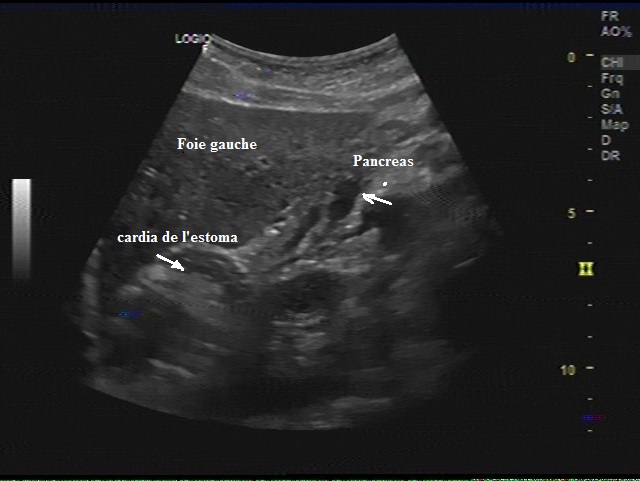

Image echographique du

pancreas en coupe sagitale ( fleche ) . Image du

\pancreas est un peu hyperechogene que le foie ,

homogene situe a inferieure du foie gauche en avant

le cardia de l'estoma |